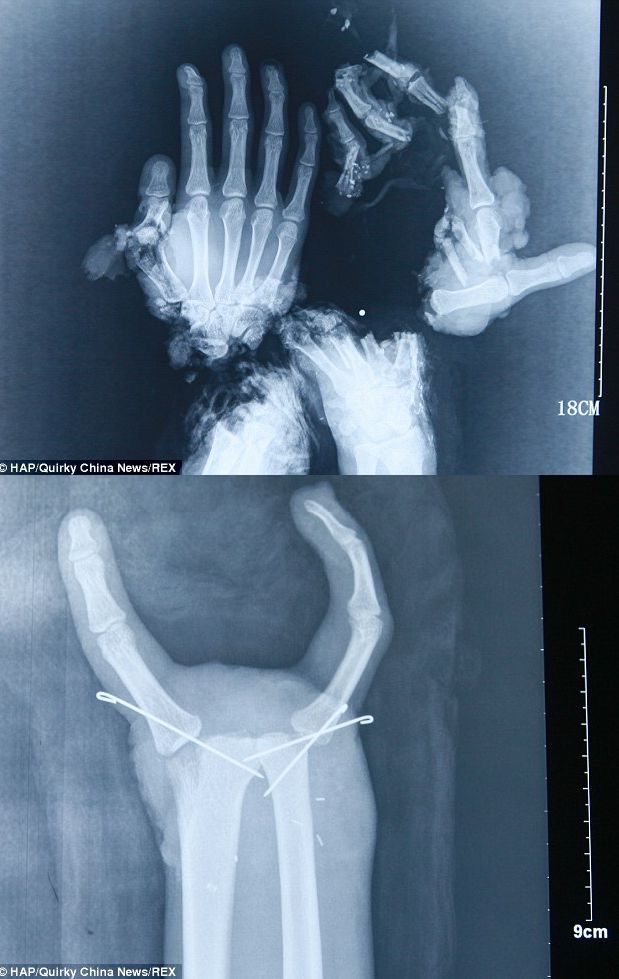

>fu6113548.jpg

>閲覧注意ね

若干やったぜ的な✌みたいになってるの不謹慎だけどじわじわ来るな…

いや実際座滅した手をここまで戻してもらったらビクトリーサインもんだけどさ

両手とは予想外だ

何したんだこの人

何で血まみれのまんまなんだよ…

まあそんなグロくはない

綺麗に縫われてるし寧ろここまで戻せるんだと感動する

中国湖南省の工場で、18歳くらいの作業員(Wang Jinさん)がハンマー機械に両手を巻き込まれる。

手首から先が切断寸前、指は複数壊滅。

病院で9時間以上の手術。壊れた指は諦めて、使える親指+小指や人差し指を移植・再固定して「2本指の機能的手」にした。

結果、物を掴む・持つ基本動作は回復。術後2週間で指を曲げられるようになったらしい